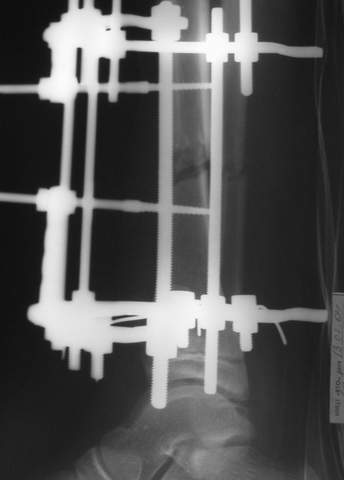

Под рукой прилагаемый пример. Как видите, "стриптиз-аппарат" (шутка проф. З.К.Башурова): 3 кольца-2 кольца-2 полукольца. В случае, который представил Евгений, характер повреждения позволил бы сразу использовать аппарат на основе 2 колец; в крайнем случае прокс. опора м.б. демонтирована сразу после репозиции.

АВФ -отдельная история в нашем краю, поэтому последний вариант -открытая репозиция, что я и сделал: Без мобилизации отломков б.б. репозиция м.б. не получалась. Первым делом фиксировал перелом м.б. кости пластиной на 4 4,5 мм винтах,

при ревизии зоны перелома б.б. кости сохранялось смещение дистального отломка кпереди, пришлось принять меры и решить эту проблему.

На прямой проекции видно угловое смещение отломков малоберцовой кости, обуславливающий и

наклон тарана, да и вальгус отломков б.б. , а на боковой проекции -смещение отломков

кпереди и по длине.

Коррекция углового смещения и смещения по длине отломков м.б. кости автоматом устраняет

наклон тарана , что необходимо для нормальной функции голеностопа. Так оно и произошло во

время операции.

Единственный момент, о котором я и уже писал - не наступило спонтанной анатомичной

репозиции отломков б.б., поэтому после репозиции пришлось использовать тягловый винт и

*укрепить* достигнутое положение узкой пластиной динамической компрессии.

Послеоперационные снимки сегодня посмотрел - все выглядит вполне анатомично, кроме длины

винтов на м.б. кость - слегка переборщил:-(( Не было камеры с собой , но как только

пересниму картинки обязательно вышлю.

Поэтому фиксация м.б. кости все-таки показана....

Помятуя наш недавний разговор о фиксации м.б. кост, высылаю послеоперационные картинки..

Напомню- разбирали случай 17 летнего молодого человека перелом дист тиб.фиб. хирургия после 3 недель с момента травмы( безуспешные попытки закрытой репозиции) Раны заживают первичным натяжением, занимается физиотерапией, пока никаких проблем не наблюдается

Как ты тут оцениваешь восстановление оси большеберцовой кости?

Отправитель: Evgueny Tchekashkine 01 Апрель 2005, 22:45

Согласный я с тобой:-)) есть остаточная вальгусная деформация (по снимку видно перекрывание дист. фрагментом б.б по латеральной поверхности проксимальноо фагмента на 2-3 мм и наружная лодыжка репонирована с укорочением, судя по прямой проекции. Необходимость использования интраоперационно дистрактора была бы оправдана (вручную было непросто *вытянуть* дистальный отломок.)

На мой взгляд, Ваша демонстрация неожиданно добавила перцу. Если память мне не изменяет, я говорил об отсутствии показаний к остеосинтезу малоберцовой.

Сейчас можно заикнуться о вредности этой манипуляции с точки зрения риска фиксации в неправильном положении, как это получилось у Вашего пациента. Сначала фиксировали большеберцовую, и надо было на этом остановиться, ин май хамбл опиньон. Потом при закручивании винтов на мощнейшей второй пластине сустав увело на вальгус. С учетом того, что пацану всего 17, я бы удалил пластину с малоберцовой и попытался тем или иным способом устранить смещение, пока не срослось.